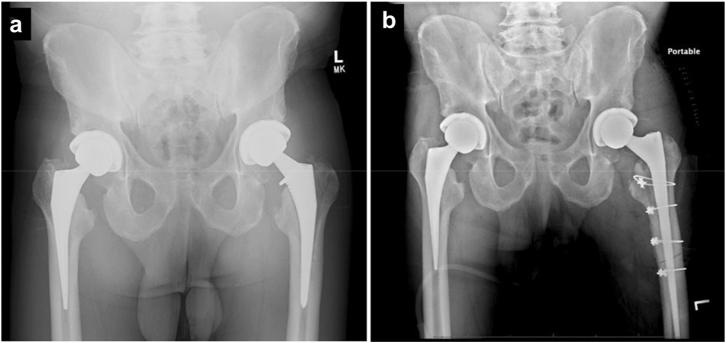

This report describes a medial calcar episiotomy with partial anterior transfemoral osteotomy of the proximal femur to aid in removal of a femoral component in setting of revision total hip arthroplasty through a direct anterior approach. Revision total hip arthroplasty is challenging, labor-intensive, and carries high complication rates. Previously described techniques such as extended trochanteric osteotomies can be utilized to facilitate removal of fixed femoral stems. The technique herein described was performed in an effort to avoid the morbidity of additional dissection and risk of nonunion associated with complete osteotomy of the trochanteric region. We present a novel technique to aid in the removal of a fixed femoral stem in the setting of revision total hip arthroplasty through an anterior approach. This technique has not previously been described specifically in the literature and was performed safely and effectively for this patient. A complication-free outcome with osteotomy union was achieved on a final follow-up of 13 months.

本报告描述了一种内侧股骨距会阴切开术,同时对股骨近端进行部分经股骨截骨术,以协助在通过直接前路进行翻修全髋关节置换术时取出股骨假体。翻修全髋关节置换术具有挑战性、劳动强度大且并发症发生率高。先前描述的技术,如延长转子截骨术,可用于便于取出固定的股骨干。本文所述技术旨在避免额外解剖带来的并发症以及与转子区完全截骨相关的不愈合风险。我们提出了一种新技术,以协助通过前路在翻修全髋关节置换术中取出固定的股骨干。该技术此前在文献中未被专门描述,且对该患者安全有效。在最后13个月的随访中实现了截骨愈合且无并发症的结果。